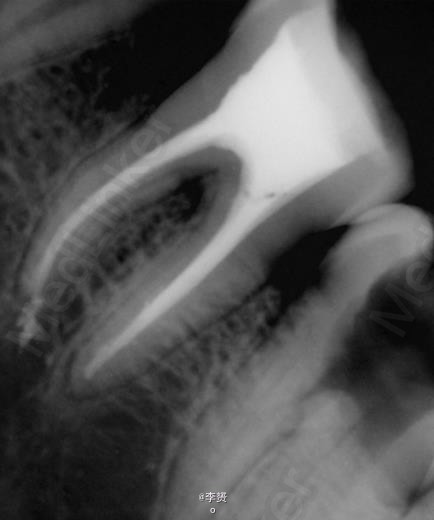

在显微镜下进行断针取出

效果很好,疼痛去除,患者满意。